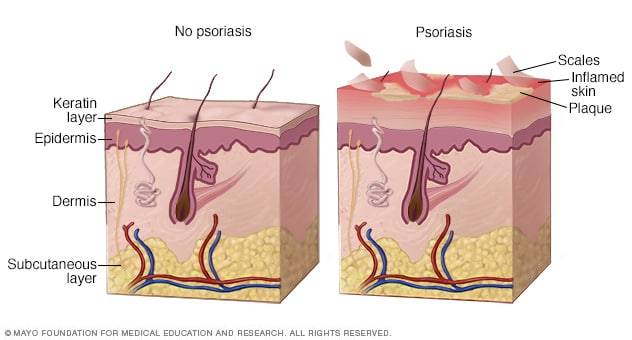

Cada 29 de Octubre se conmemora el día mundial de la Psoriasis con el objetivo de saber más sobre esta enfermedad cutánea autoinmune crónica que causa áreas rojas y escamosas, provocando dolor, molestias y estigmatización social.

La Psoriasis es una enfermedad frecuente y crónica por no tener cura al día de hoy. Puede ser dolorosa, interferir en el sueño y dificultar la concentración. Esta afección suele presentarse sobre todo en las rodillas, los codos, el tronco y el cuero cabelludo; en ciclos, con brotes que duran algunas semanas o meses y luego disminuyen. Los factores desencadenantes comunes en las personas con predisposición genética a la psoriasis incluyen infecciones, cortes o quemaduras y determinados medicamentos.

Síntomas comunes de la Psoriasis:

- Una erupción irregular cuyo aspecto varía mucho de persona a persona, desde unos pocos puntos de escamas similares a la caspa hasta erupciones importantes en gran parte del cuerpo

- Erupciones que varían en color y tienden a ser de tonos violáceos con escamas grises en pieles morenas o negras, o de tonos rosados o rojizos con escamas plateadas en pieles blancas

- Piel agrietada y seca que es posible que sangre

- Psoriasis en placas. El tipo de psoriasis más común, la psoriasis en placas, produce manchas secas y elevadas en la piel (placas) que provocan picazón y están cubiertas de escamas. Pueden aparecer unas pocas o muchas. Suelen aparecer en los codos, las rodillas, la región lumbar y el cuero cabelludo. Las manchas pueden ser de distintos colores, según el tono de piel. La piel afectada puede curarse con cambios de color temporales (hiperpigmentación posinflamatoria), en especial en pieles morenas o negras.